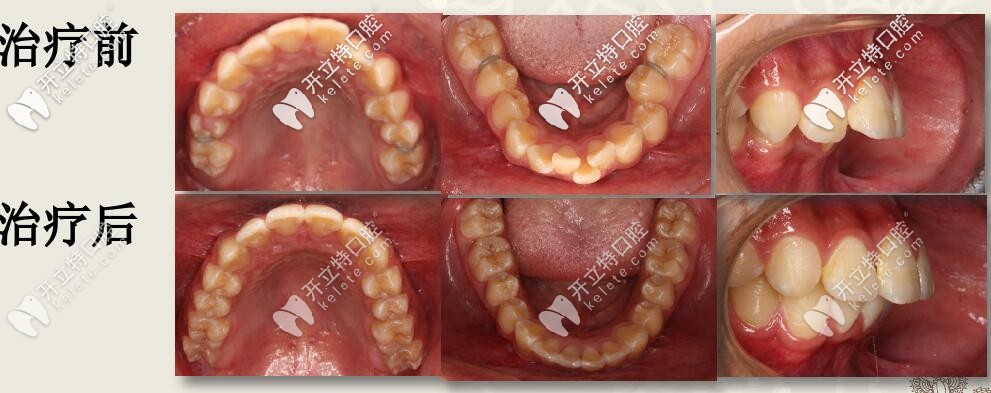

深復(fù)蓋凸嘴伴下巴后縮,直絲弓聯(lián)合擴(kuò)弓,斜導(dǎo)矯正27個(gè)月對(duì)比

12歲兒童齙牙,下巴后縮,牙列擁擠,全口直絲弓配合斜導(dǎo)、擴(kuò)弓器以及激動(dòng)器矯治,27個(gè)月后效果驚人。

今天西安圣貝牙科分享一例12歲兒童齙牙矯正案例,深覆蓋伴隨深覆合,采用雙期聯(lián)合配合肌激動(dòng)器矯治,矯治醫(yī)生是圣貝口腔何曉天醫(yī)生。

肉眼可見(jiàn)上前牙唇傾,輕度擁擠 下頜牙弓寬度窄,前牙區(qū)擁擠,后牙去舌傾明顯,前牙深覆蓋,深覆合

結(jié)束后,牙列整齊,深復(fù)蓋明顯改善。